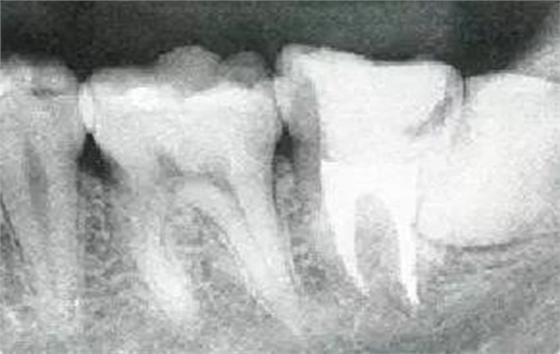

參考病例① 35歲女性

在左下第一磨牙在25歲時(shí)近中處可以看到垂直性的骨吸收,但35歲時(shí)吸收停止,原本沒(méi)有見(jiàn)到的遠(yuǎn)中處骨吸收的,現(xiàn)在卻吸收得很嚴(yán)重。

在右下處,原本有大量骨吸收的第一磨牙處的吸收卻變緩慢,原本沒(méi)有吸收的第二前磨牙卻出現(xiàn)了吸收。出現(xiàn)吸收的左上第一磨牙的遠(yuǎn)中處,吸收得越來(lái)越多了。

把10年間的變化做成表格。牙周病的發(fā)展根據(jù)各個(gè)人會(huì)不同,即使通一個(gè)人,不同牙齒,不同牙面發(fā)展的狀態(tài)也不同。